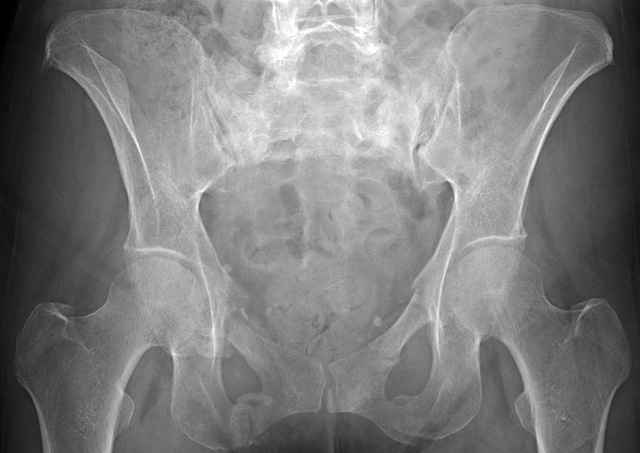

Here are a recent patient’s example slides...

54 yo Female Fell c/o Pain

Initial Films

?Instability on Exam - Limited by Pain

NonOp Initial Mgmt

Pelvic CT Scan - 3 Months After Fall

Sacral Injuries

Ramus Fractures